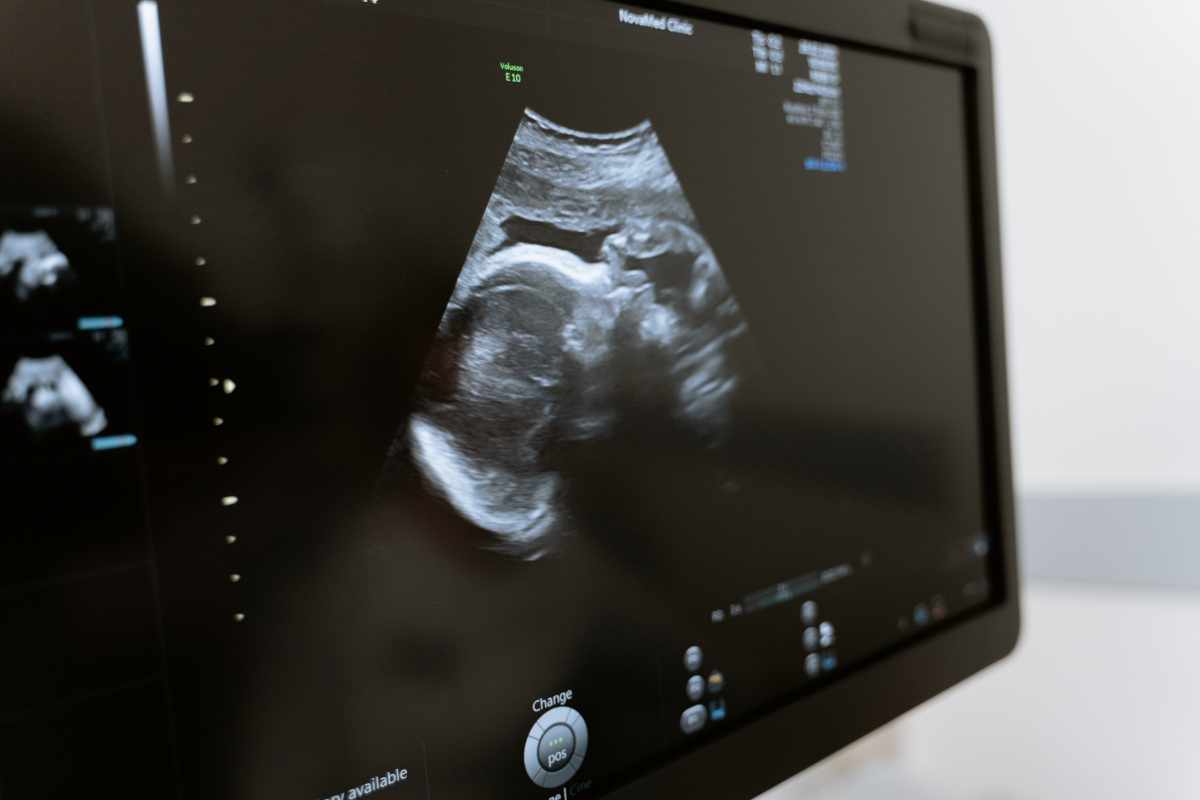

Pregnancy is filled with exciting milestones, and one of the most magical is feeling your baby move for the first time. These initial sensations can bring a sense of connection and reassurance, but it’s natural to have questions about when and how this happens. Here’s a guide to understanding your baby’s movements during pregnancy.

Most parents-to-be experience their baby’s first movements, often called “quickening,” between weeks 16 and 25 of pregnancy. For first-time moms, this may happen closer to week 20, while those who have been pregnant before might notice movements earlier. These initial flutters are usually gentle and can feel like: